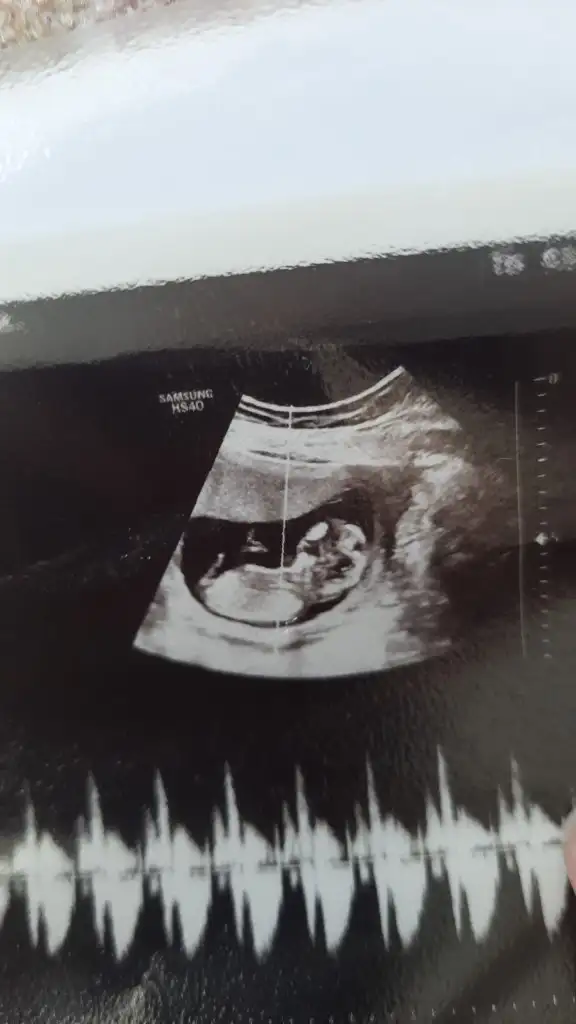

Bana da tahminde bulunurmusunuz abla 12 haftalık ^-^Ultrason resmi varsa 11 ile 13 arası nub belli ise bizde tahminde bulunabiliriz

Nubu düz gidiyor. Nub teorisine göre kız bebekBana da tahminde bulunurmusunuz abla 12 haftalık ^-^

Yaa teşekkür ederim onu anlamıyorum nubuz ne bilmiyorum yine de sağolunNubu düz gidiyor. Nub teorisine göre kız bebek

Rica etsem banada bakabilir misiniz şuan 13+3 teyiz 11. Haftada kıza benziyor denildi ama ben erkek hissediyorum nedenseNubu düz gidiyor. Nub teorisine göre kız bebek